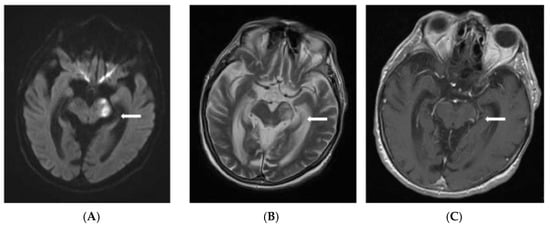

Fungal endocarditis, despite being a rare diagnosis, has a higher morbidity and mortality rate compared to bacterial endocarditis. Candida species are the most common isolated pathogens involved in fungal endocarditis. Diagnosis is suspected in patients with underlying conditions such as cancer, myelodysplastic syndrome, diabetes, or intravascular catheters, where the modified Duke criteria apply. Management of the patient requires a multidisciplinary team (cardiologist, infectious diseases consultant, cardiac surgeon) along with antifungal treatment. We present the case of a 60-year-old male with biological prosthetic aortic valve replacement in the previous year for bicuspid aortic stenosis, admitted for a 5-day history of fever, nausea and minor urinary symptoms. The blood cultures were positive for Candida parapsilosis. Transthoracic cardiac ultrasound revealed a hypoechogenic mass attached to the aortic valve at the prosthetic fixation site. Although diagnosis was rapidly confirmed and treatment was administered shortly after first suspected, the patient developed, at first, cavernous sinus thrombosis and, later, fatal ST elevation myocardial infarction. The patient died despite efficient antifungal therapy, initially with Anidulafungin in monotherapy and later in combination with Fluconazole. The reported case emphasizes the importance of managing fungal endocarditis, the need for urgent diagnostic attention and multidisciplinary team approach by infectious diseases specialist, cardiologist, neurologist and heart surgeon.

Figure 1